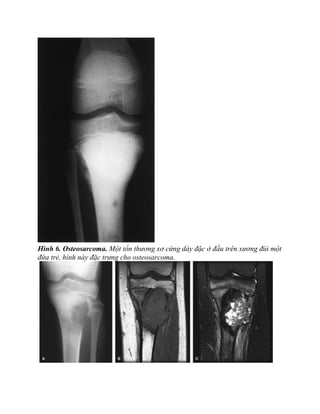

Hình 6. Osteosarcoma. Một tổn thương xơ cứng dày đặc ở đầu trên xương đùi một

đứa trẻ, hình này đặc trưng cho osteosarcoma.